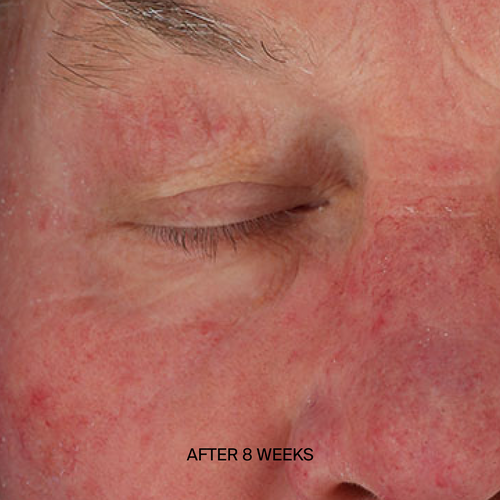

From cellular repair to dramatic, visible changes